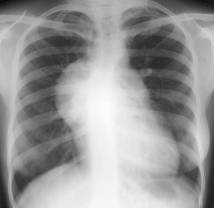

REVĂRSATUL PERICARDIC

De la 300-500 ml se evidentiaza radiologic. Umbra cardiaca este marita bilateral, mai ales spre stânga, având un aspect triunghiular. Cele doua margini ale opacitatii cardiace se indeparteaza, descriind arcuri mari convexe spre diafragm. Raportul cardio-toracic e inversat. Uneori, în interiorul acestei mase opace se distinge o opacitate mai intensa, care reprezinta opacitatea cordului, realizându-se în felul acesta un contur dublu.